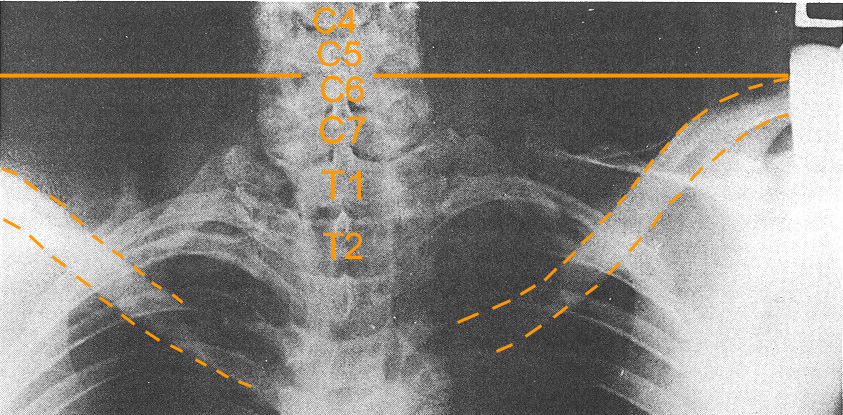

This same anatomical orientation is seen in the AP cervicothoracic x-ray taken of President Kennedy at the time of autopsy. However, you cannot see the superior margins of the collarbones where they attach to the acromion process of the shoulder blade, making the A-C joint of the shoulder. See below.

A line drawn from the superior margin of the left shoulder tip (on your right) drawn horizontally through the spine places it at C5-6. This corresponds nicely with the autopsy photograph taken of the rear of President Kennedy's back, with the wound below the level of the shoulder, yet corresponding to a lower neck/upper back wound. With this type of shoulder elevation, only minimal 'bunching' would be needed to compensate for the discrepancy noted by numerous conspiracy theorists because his clothing would be elevated due to the shoulder height. Nevertheless, one cannot know Kennedy's exact posture, but the autopsy photos indicate, at least at the time of autopsy, his shoulders were quite elevated, giving the false impression that the wound is at a lower point such as T3 or T4.